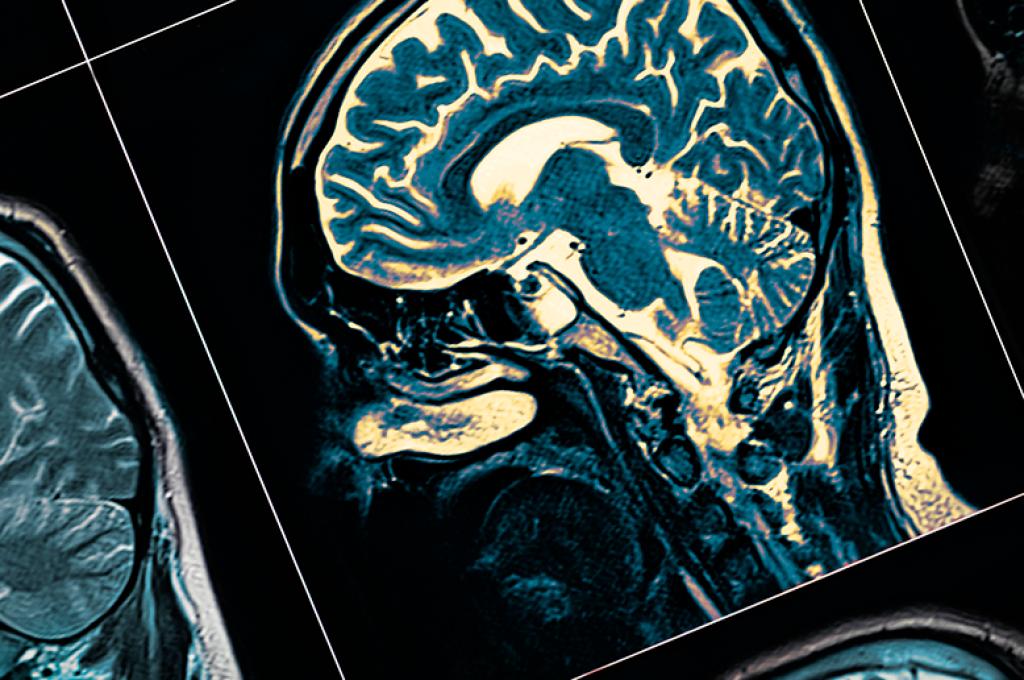

The project’s new infrastructure includes a super-powered MRI — one of just three in Canada — that can reveal in high-resolution detail the damage wrought by various illnesses, says Hynynen. Unlike standard MRIs, it can pick up tiny tumours and the beginnings of Alzheimer’s brain cell plaques. It also gives a very detailed image of the brain’s fiber networks, presenting surgeons with more precise targets than ever before.